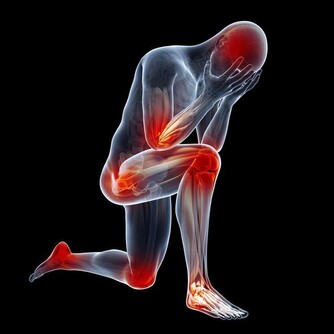

5.體重下降,乏力:

當肝臟受損後,肝臟無法為身體提供能量,導致虛弱和肌肉萎縮,從而使得病人的體重發生驟減的現象。部分肝硬化早期可出現乏力、食慾減退,消化不良,噁心,嘔吐,右上腹隱痛和腹瀉等症狀。